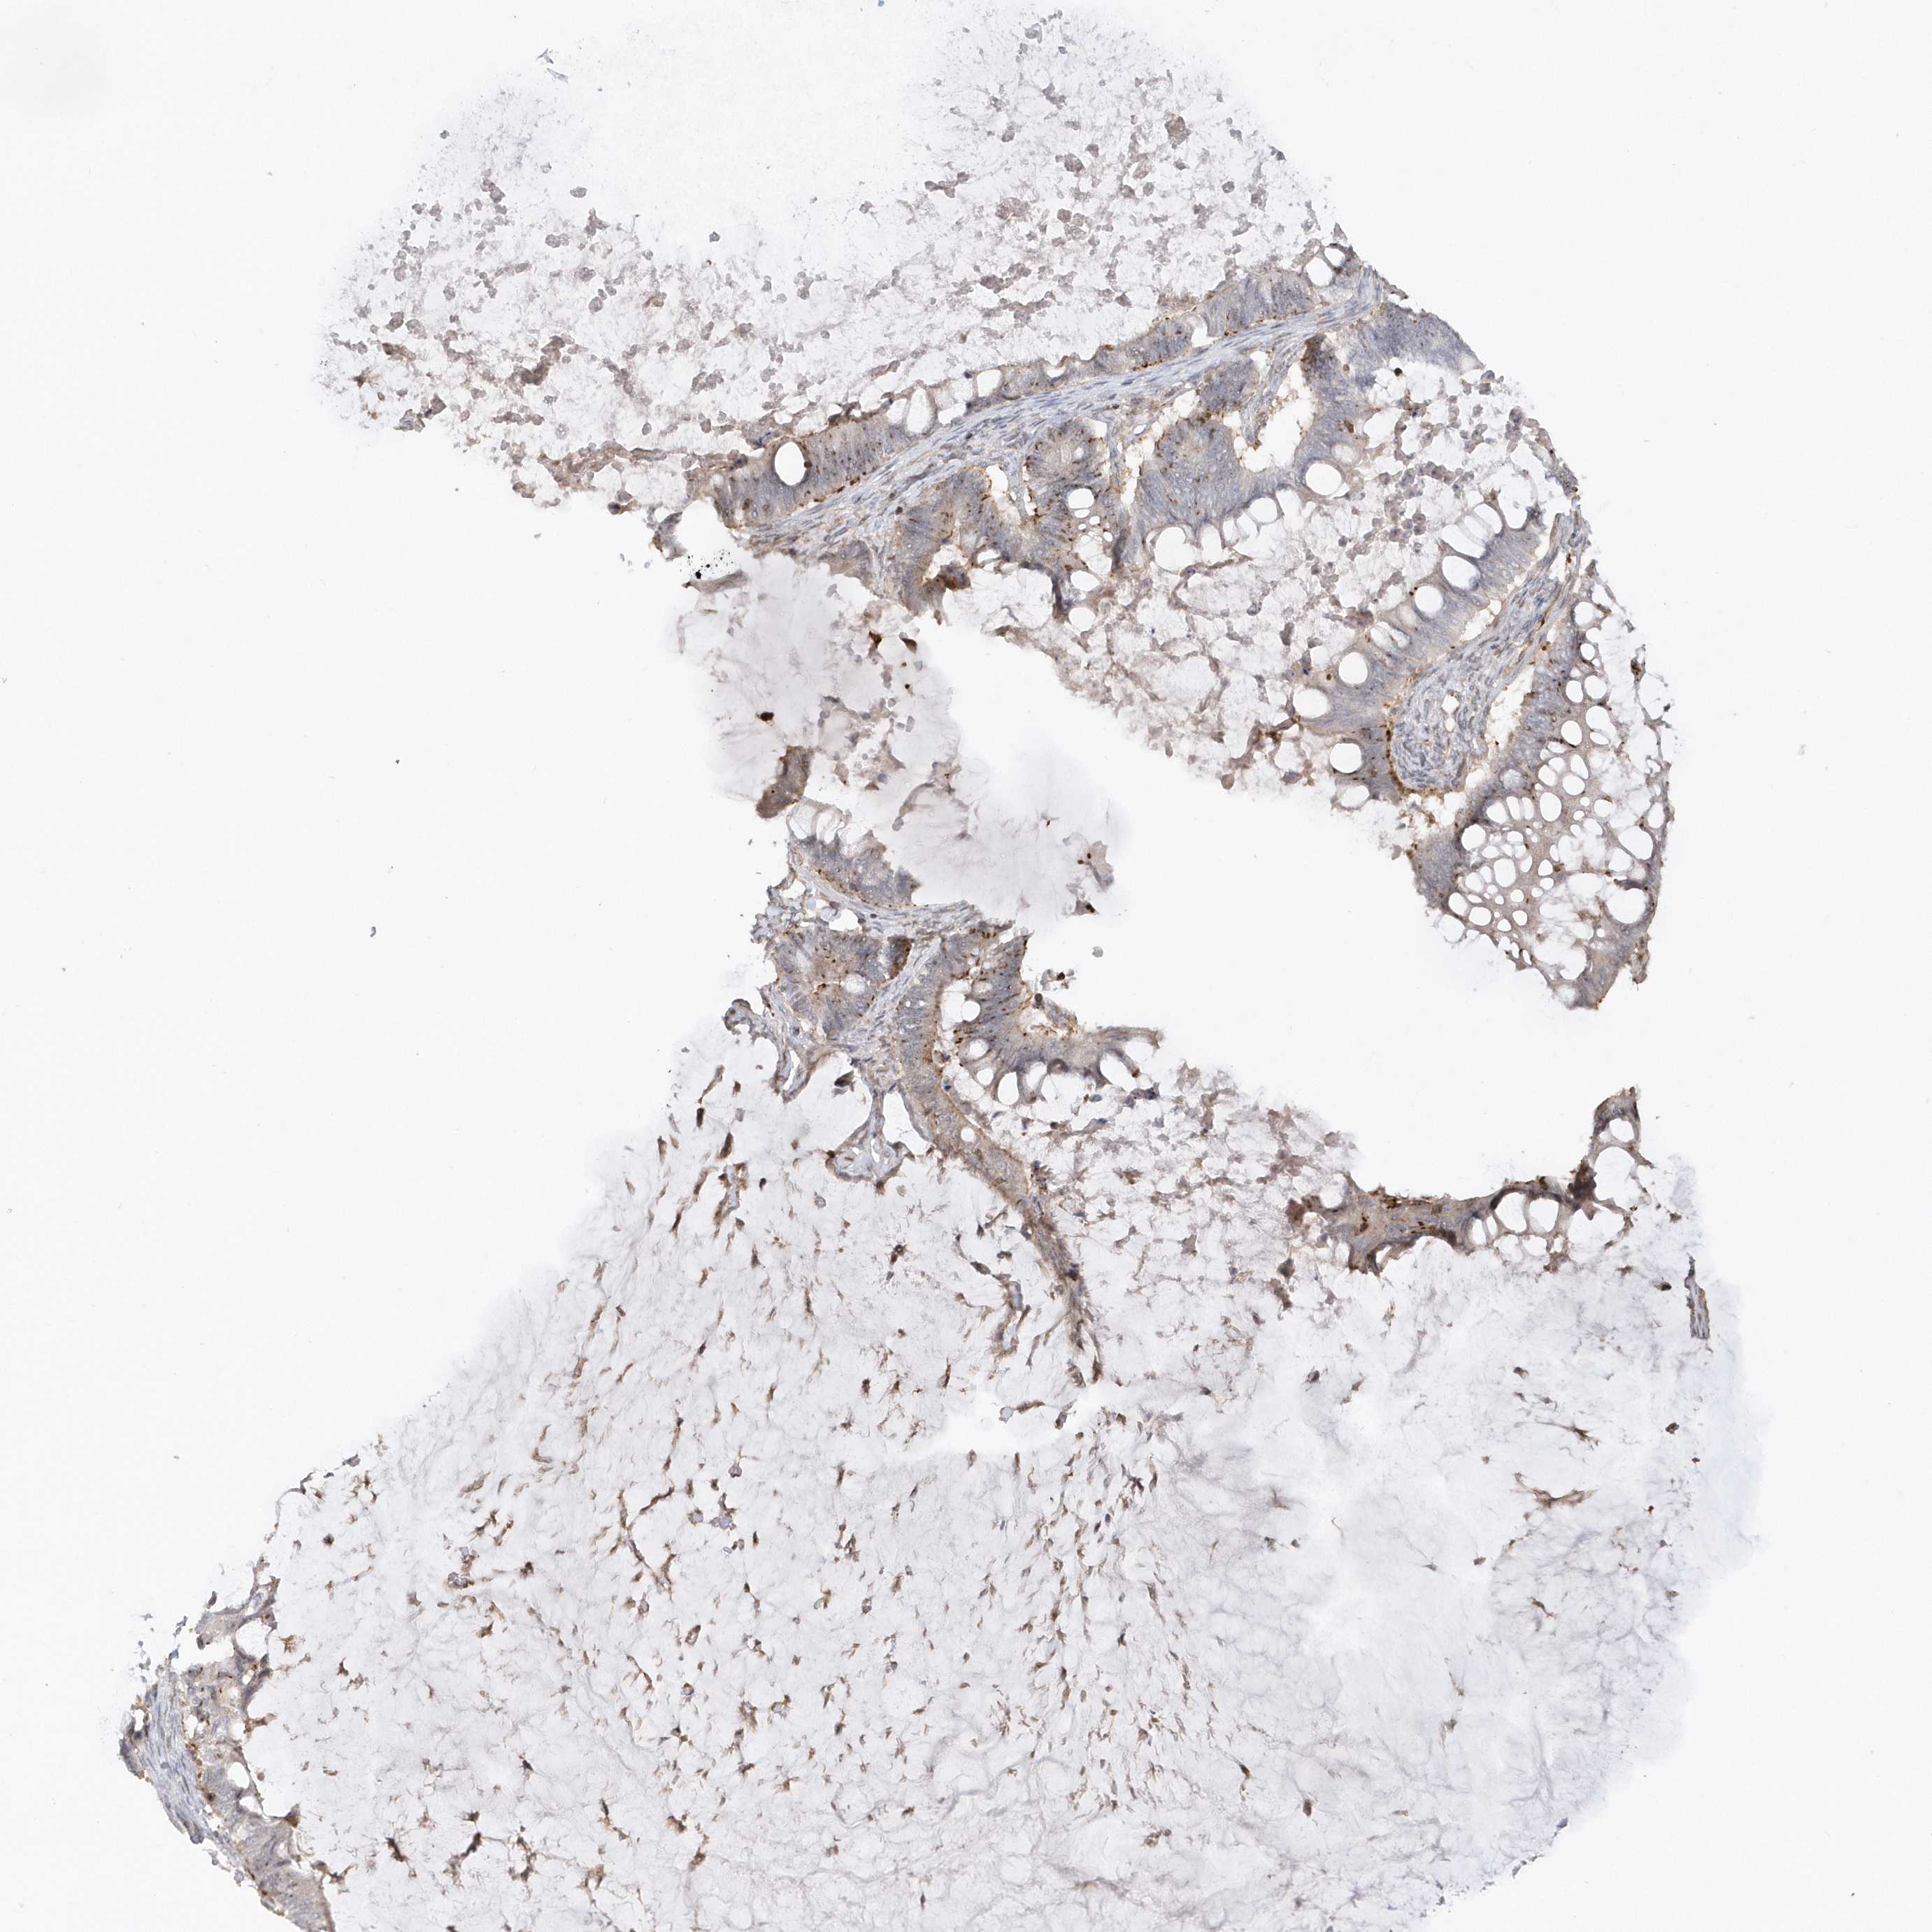

OVARIAN CANCER - Protein expressioni

A mouse-over function shows sample information and annotation data. Click on an image to view it in a full screen mode. Samples can be filtered based on level of antibody staining by selecting one or several of the following categories: high, medium, low and not detected. The assay and annotation is described here.

Note that samples used for immunohistochemistry by the Human Protein Atlas do not correspond to samples in the TCGA dataset.

Antibody stainingi

Antibody staining in the annotated cell types in the current human tissue is reported as not detected, low, medium, or high, based on conventional immunohistochemistry profiling in selected tissues. This score is based on the combination of the staining intensity and fraction of stained cells.

Each image is clickable and will lead to virtual microscopy that enables deeper exploration of all samples and also displays staining intensity scores, fraction scores and subcellular localization as well as patient and tissue information for each sample.

Antibody HPA034757

Cystadenocarcinoma, serous, NOS

Carcinoma, endometroid

Cystadenocarcinoma, mucinous, NOS

Carcinoma, NOS